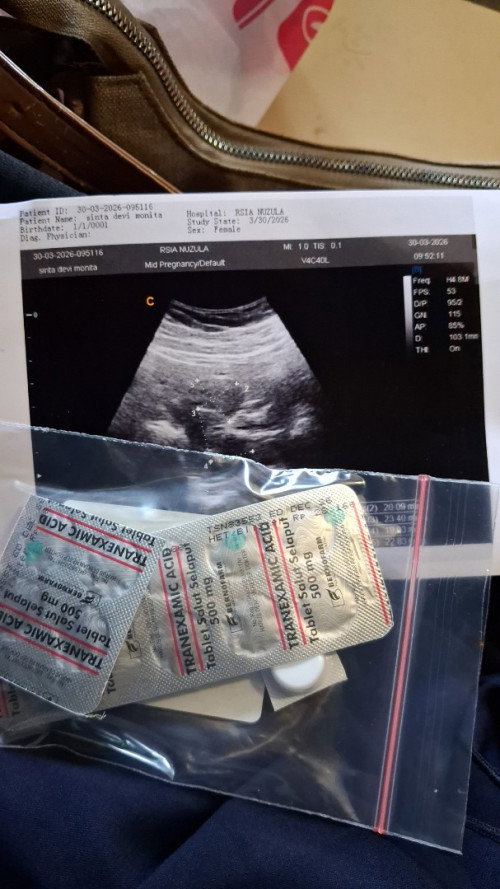

Jadi gini bun tahun lalu bulan november 2025 aku memutuskan kb3 bulan berhenti. Trus selama berhenti aku ngflek trus dalam artian ada hari ngeflek 2 hari dalam satu minggu. Dan trus berulang. Ada hari dimana habis berhubungan paginya keluar flek lagi . Sampai akhirnya pas bulan maret sebelum lebaran 3 hari ngflek sampai hari ini di hitung sudah 15 hari ngflek trus bukan hanya ngflek tapi ada dimana agak deres juga. Kemarin sudah ke dokter obgyn tapi di usg gak ada tanda kehamilan dan menurut dokternya itu masalah gak cocok di kb nya. Nah bunda ada yang pernah ngalamin? Terus tolong dong bun obat apa yang berhentiin flek ini? Sudah dikasih obat tapi belum berhenti-henti fleknya. Jadi kalau mau ibadah jadi ragu . #mohonbantujawabbunda #Sharingdong_Bund #bantujawab #sharing